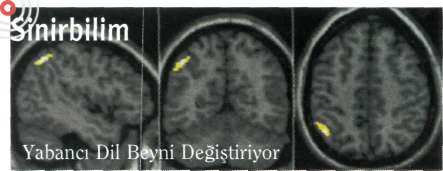

Birden fazla dil öğrenebilme, insanlara özgü bir yetenek. Bu yeteneğin, beyinde oluşan bazı işlevsel biçim değişiklikleri ile sağlandığı sanılıyor. Şimdiyse İngiliz ve İtalyan biliminsanları, ikinci bir dil öğrenmenin, beynin sol yarıküresinde, yanal lobun alt kısmındaki gri madde yoğunluğunu artırdığını ortaya koydular. Wellcome Görüntülemeli Nöroloji Bölümü araştırmacılarından Andrea Mechelli başkanlığındaki ekip, yaşları 2 ile 34 arasında değişen 110 denek üzerinde yürütülen deneylerin ayrıca, bu bölgedeki

|

yeniden yapılanma derecesinin, yeni dili öğrenmede erişilen düzey ve öğrenme yaşıyla yakın ilişkisini belirledi. Araştırmacıların Nature dergisinde yayımladıkları deney sonuçlan, iki dil konuşanların sol alt yanal beyin kabuklanndaki gri madde yoğunluğunun, yalnızca ana dilini konuşanlannkine göre zaman içinde arttığını, ve bu artışın küçük yaşta dil öğrenenlerde daha belirgin olduğunu ortaya koydu.

Nature, 14 Ekim 2004